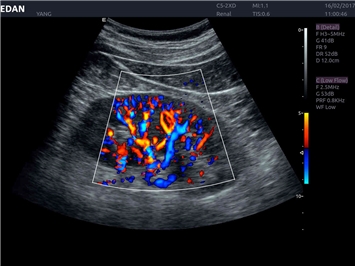

• Общей визуализации

Энергетический допплер:

Да

Трехмерная реконструкция ЦДК: